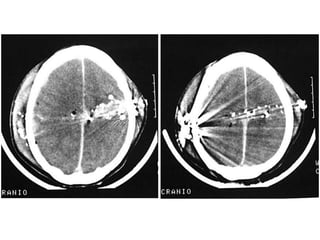

Angiografia do Crânio

• Exame radiográfico após injeção

de contraste;

• Alta densidade tissular não resulta

em resolução de contraste.

   Doenças da substância branca;

   Neoplasias;

   Doenças infecciosas;

   Distúrbios hemorrágicos;

   Distúrbios isquêmicos.